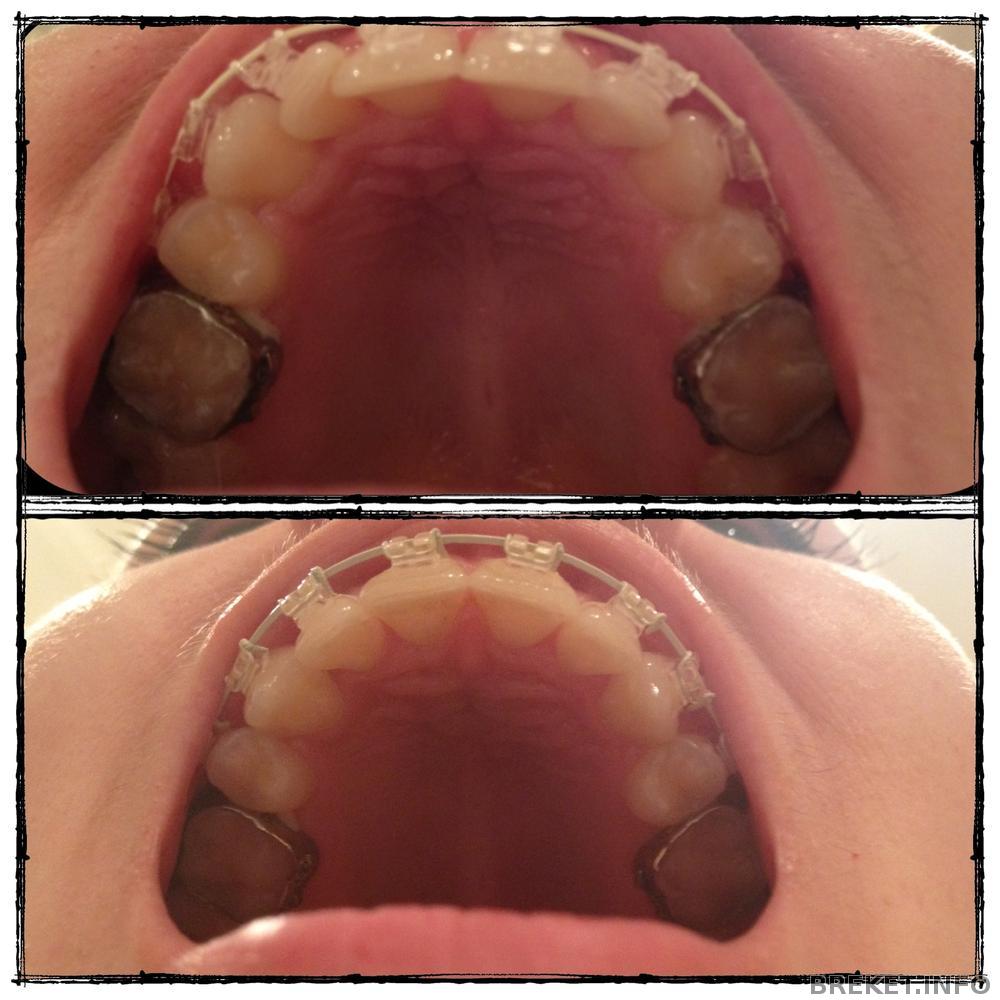

Ну вот и я полностью укомплектована!)) Установка на НЧ, сепарация и тяги

day 20

Вчера был очень плодотворный прием. Установили брекеты на НЧ, посепарировали 5-ку (процедура та еще, беее, у меня аж настроение после нее испортилось ), еще выдали тяги и сказали носить их круглосуточно.. Брекеты особо не трут, десна после сепарации почти зажила, но вот тяги - это жесть... Они вроде слабенькие, а зубы из-за них ТАК ноют!( Хотя мне грех жаловаться, процесс-то вроде идет и это главное, остальное - мелочи